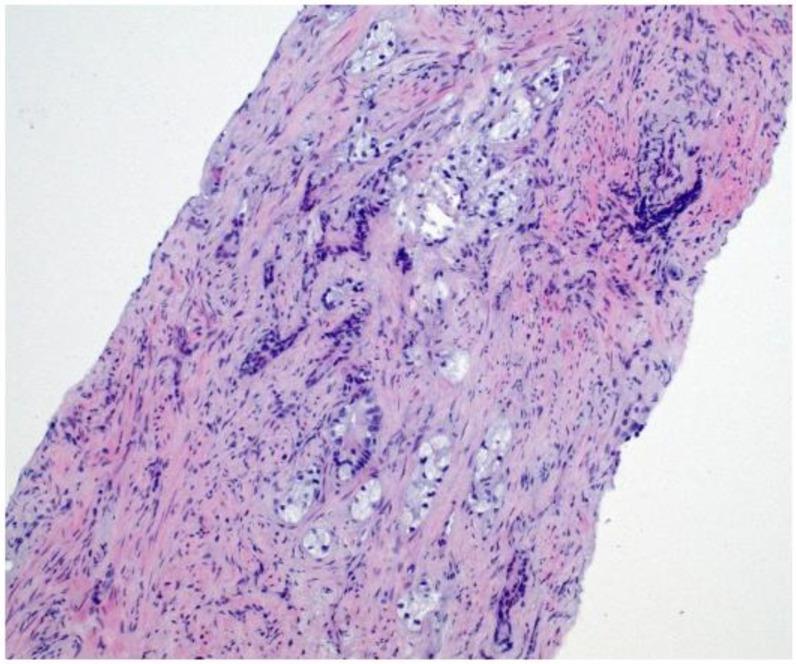

我们描述了一名77岁男性,他出现劳力性呼吸困难和间歇性咳嗽,最初提示心肺病因。影像学检查发现多个胸膜结节和广泛的右侧胸腔积液。尽管血清前列腺特异性抗原(PSA)水平临界为2.91 ng/mL,但胸膜活检的组织病理学和免疫组化结果证实为转移性前列腺腺癌。随后的影像学检查在前列腺中发现了一个PI-RADS 5类病变,活检证实为ISUP 5级组疾病(Gleason评分4 + 5 = 9)。骨扫描显示无骨转移,腹部增强CT未发现其他转移病灶。患者开始接受雄激素剥夺治疗,随后使用阿比特龙。该病例强调了前列腺癌非典型转移表现所带来的诊断挑战。低或中度升高的PSA可能会掩盖对前列腺起源的怀疑,尤其是对于提示间皮瘤的胸膜病变。包括雄激素受体、AMACR和Prostein在内的免疫组化标志物对于准确诊断至关重要。